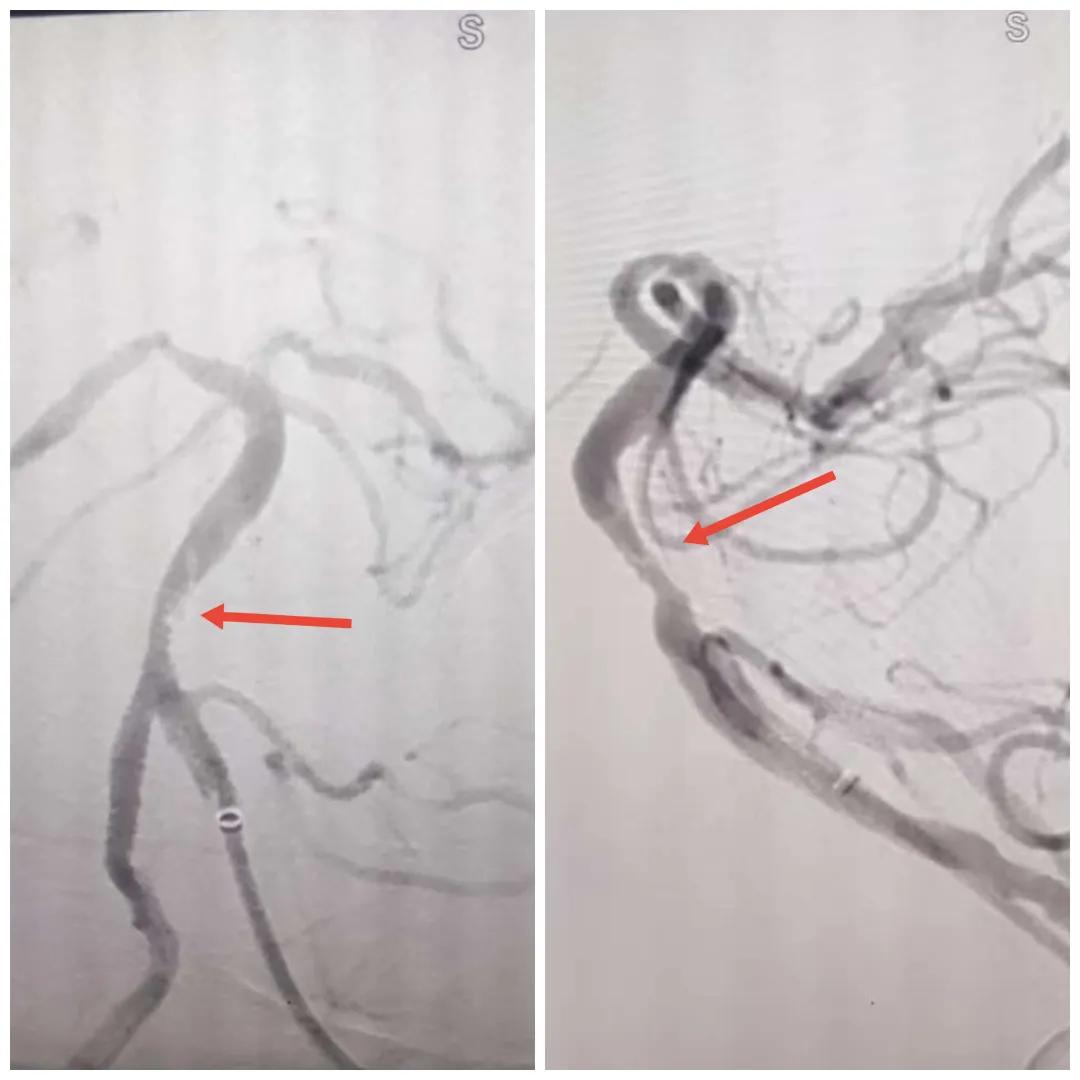

在經(jīng)造影后,主刀醫(yī)生腦一科副主任楊慶堂發(fā)現(xiàn)患者基底動脈下段重度狹窄且狹窄段以遠(yuǎn)有大負(fù)荷血栓,其狹窄處考慮為動脈夾層,手術(shù)難度及風(fēng)險(xiǎn)較大。楊慶堂副主任在彭壯副主任醫(yī)師的協(xié)助下運(yùn)用spaceman(太空人)技術(shù),中間導(dǎo)管抵近血栓抽吸配合支架拉栓,成功開通血管。再次造影可見基底動脈管腔明顯增寬,遠(yuǎn)端血管顯影良好,且等待20分鐘后造影仍顯示血流通暢。楊慶堂副主任考慮到本次手術(shù)時(shí)間不宜過長,現(xiàn)患者基底動脈及分支前向血流維持良好,給予其抗栓藥物應(yīng)用后結(jié)束手術(shù),并建議患者3個月后復(fù)查造影,明確其基底動脈夾層情況。

造影可見血管夾層和大量血栓形成

取栓后血管管腔增寬,前向血流良好